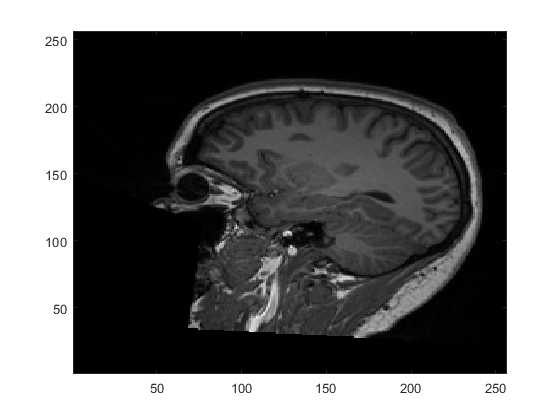

Perhaps most notable about voxel-space is that the orientation of the image is based on the storage-order of the data on disk. This is usually dictated by the scanner and can differ from image to image. As such, there are no guarantees about which direction in the image correspond to which dimensions of the data matrix. For example, if we display a single slice of the example image we loaded above, we get

figure;

imagesc(image(:,:,110)'); % transpose so x = columns and y = rows

set(gca,'YDir','normal'); % make sure y-axis is bottom -> top

colormap('gray');

Here, we are displaying the \(x\)-axis and \(y\)-axis of the image with the \(z\)-axis fixed at slice 110 (i.e. image(:,:,110)). We orient the image so that the \(x\)-axis runs horizontally and the \(y\)-axis runs vertically. From this, we can see that the \(x\)-axis corresponds to anterior-posterior, the \(y\)-axis corresponds to inferior-superior and the slices through \(z\) run left-right. This goes against the typical convention in neuroimaging, as we will see below, but is entirely determined by how the scanner chooses to collect and save the data.